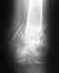

закрытый полифокальный многооскольчатый перелом средней и нижней трети правой бедренной кости со смещением обломков.

Здравствуйте, травма была получена в дтп 06.09.2012 вытяжка и подготовка до 20.09.2012 далее операция остеосинтез илизарова, потом вторая операция 22.10.2012 фиксация промежуточного отломка на двух уровнях. Скажите пожалуйста, все в порядке? Снимок последнего рентгена от 10.06.2013 приложу. Далее сделаю очередной снимок, потом выложу.http://s019.radikal.ru/i609/1308/32/7e785b467241.jpghttp://s019.radikal.ru/i619/1308/25/5747668cf4ae.jpghttp://s017.radikal.ru/i444/1308/9e/4fdc42e9cd6e.jpg